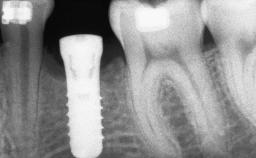

Guided Bone Regeneration (GBR) with a Particulated Autologous Graft and a ePTFE-Reinforced Membrane for Vertical Augmentation of a Single-Tooth Edentulous Space in the Esthetic Zone

A 47-year-old Caucasian woman with a single-tooth edentulous space at the site of the left maxillary canine was referred for treatment. She had undergone traumatic extraction of this impacted canine several months before referral. Her chief complaint was the dissatisfying appearance of her smile. The patient desired a stable and esthetic rehabilitation of the site. Her dental history showed no evidence of periodontal disease or bruxism. She had no systemic diseases, was not taking any medications, and did not smoke. The extraoral examination revealed a high lip line and an inadequate soft-tissue volume at the defective canine site. Large black triangles were visible between the canine and its adjacent teeth.

# of Implants 1

Type of Implants Two-Piece

Placement Protocol Early or late implant placement

Bone Volume Deficient vertically or deficient vertically AND horizontally